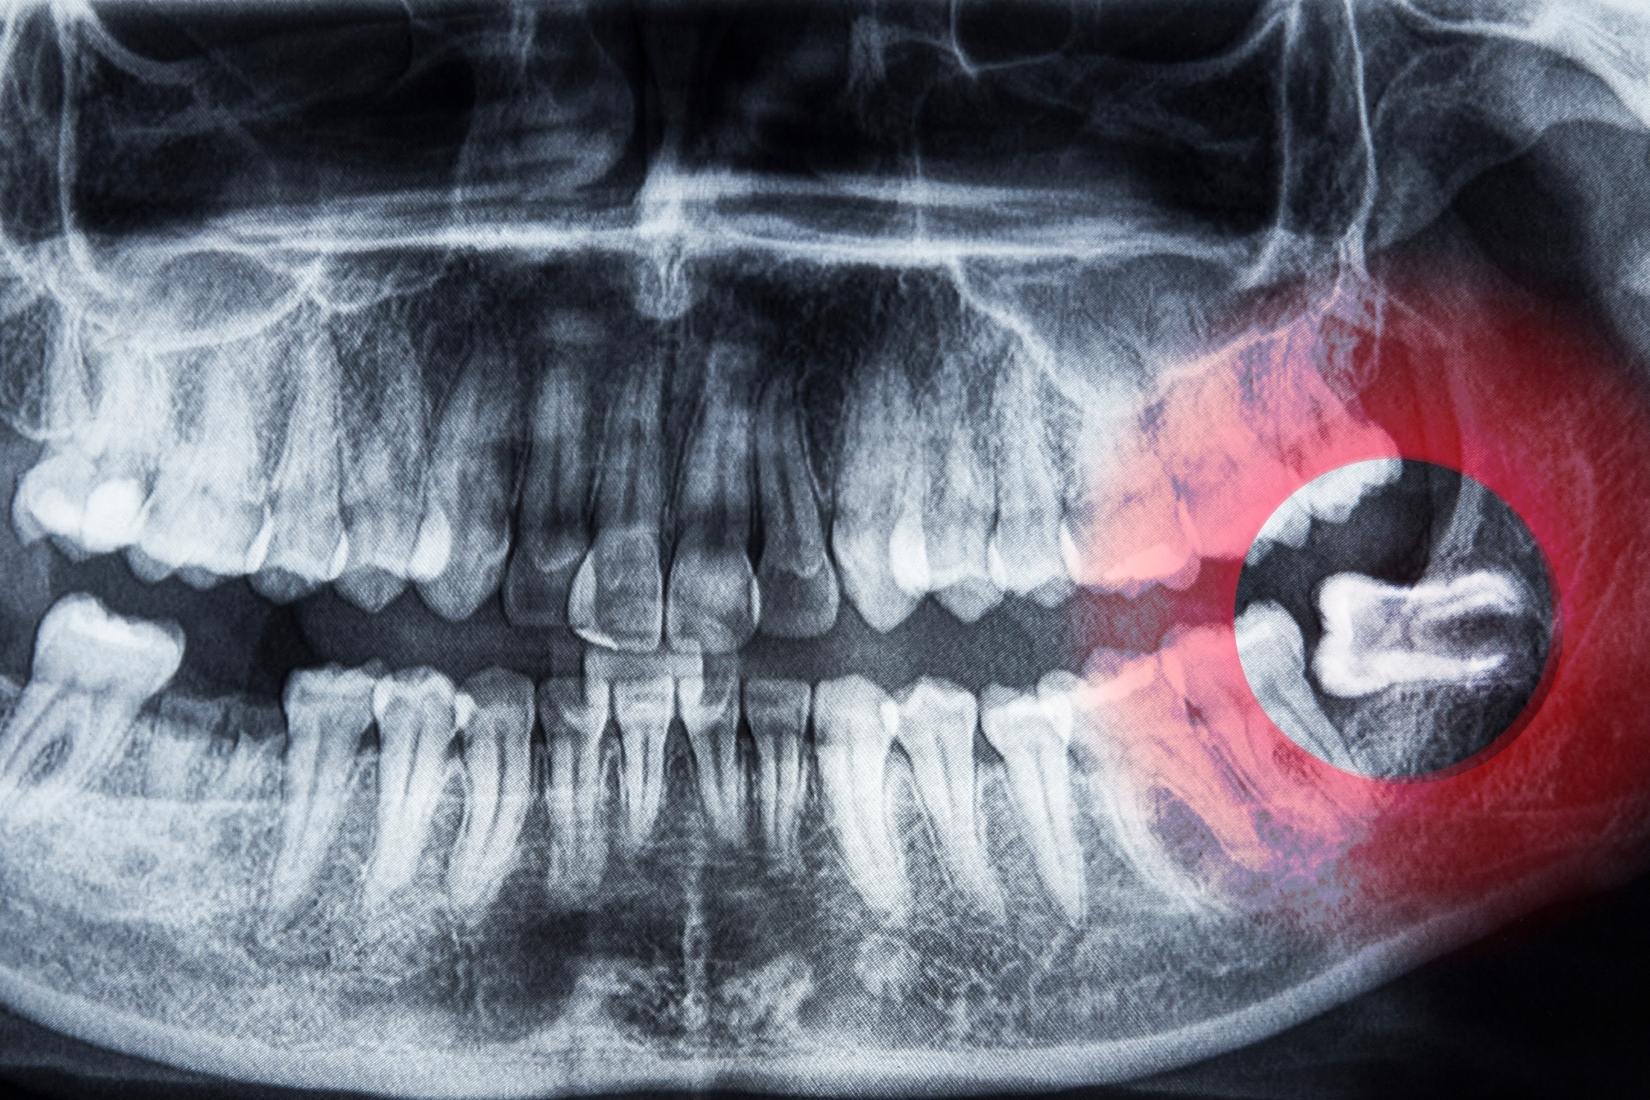

Alt ve üst çenede 20 yaş dişlerinin konumunu ve sürme şekillerini gösteren bilgilendirici diş anatomisi görseli.

20 yaş dişleri, ağızda en son süren üçüncü büyük azı dişleridir. Diş hekimliği literatüründe “üçüncü molar dişler” olarak adlandırılırlar. Çoğunlukla:

• 17–25 yaş aralığında

• Alt ve üst çenede

• Toplamda dört adet

olarak sürmeleri beklenir. Ancak her bireyde bu dişlerin sürme zamanı, sayısı ve konumu farklılık gösterebilir.

Gömülü 20 Yaş Dişi Ne Anlama Gelir?

20 yaş dişi, çene kemiği veya diş eti altında kalarak ağız içine tam olarak süremediğinde “gömülü diş” olarak tanımlanır. Gömülü dişler:

• Tamamen kemik içinde

• Kısmen kemik içinde

• Diş eti altında

konumlanabilir. Her gömülü diş mutlaka sorun oluşturmaz; ancak bazı durumlarda takip edilmesi gerekir.